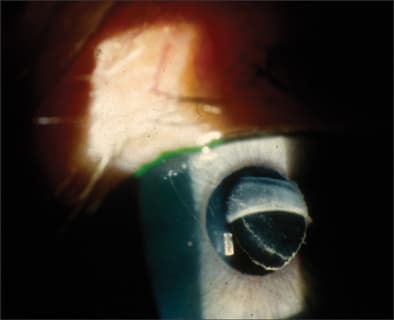

An additional postoperative complication that can occur during phacoemulsification is obstruction of the drainage device with lens material or vitreous (Figure 4). Some surgeons routinely place a suture or other plug into the tube ostomy to protect against lens material and viscoelastic during phacoemulsification.32 Other surgeons avoid the open tube and perform cataract surgery as if it were not present.33 Another concern in this group is late corneal decompensation, which can have the appearance of pseudophakic bullous keratopathy, except for the segmental nature. Touch between the cornea and tube — either at rest, with eye rubbing, or with blinking — leads to progressive endothelial cell loss and decreased ability to clear the stroma. Bhattacharyya et al. reported 27% of their patients developing irreversible corneal edema, Gujral et al. encountered a rate of 9%, and Erie et al. had no patients with corneal edema.31,33,34 Ensuring no corneal-tube touch greatly increases the chances of avoiding this complication.

Figure 4. Drainage device tube blocked by vitreous following complicated cataract surgery.